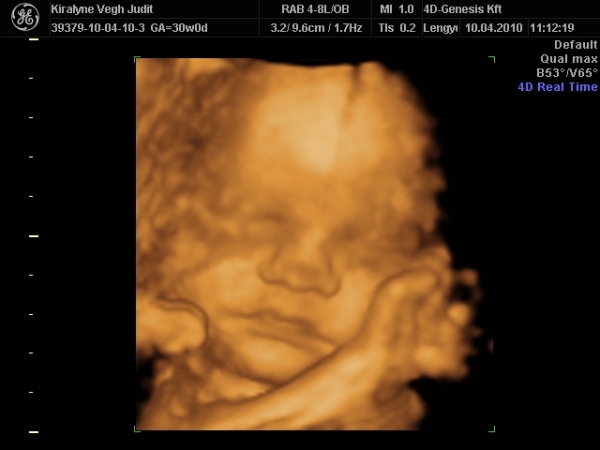

4D-re holnap megyünk 11-re, utána meg tervezünk egy kis csavargást. :lol: :lol: :lol:

Ma jól elfáradtam. Voltunk 4D-n, a várban és a Csodák palotájában. Rengeteget sétáltunk, nem érzem a lábamat.

A lényeg, hogy Izi baba nagyon jól van,

Babócám fejjel lefele, idézem: "méhlepény olyan távol van a méhszájtól, mint Makó Jeruzsálemtől." :oops: :oops: :oops:

Szóval nem értem a szerdai uh-ot. :oops: :oops:

"0" fokban érett a lepény, 1741g kis csöppségem, combcsont mérete alapján már 32 hetesnek felel meg. Amúgy minden mérete alapján 1 héttel idősebb. Magzatvíz átlagos. És tiszta apja. :lol: :lol: :lol: :lol:

És a képek.